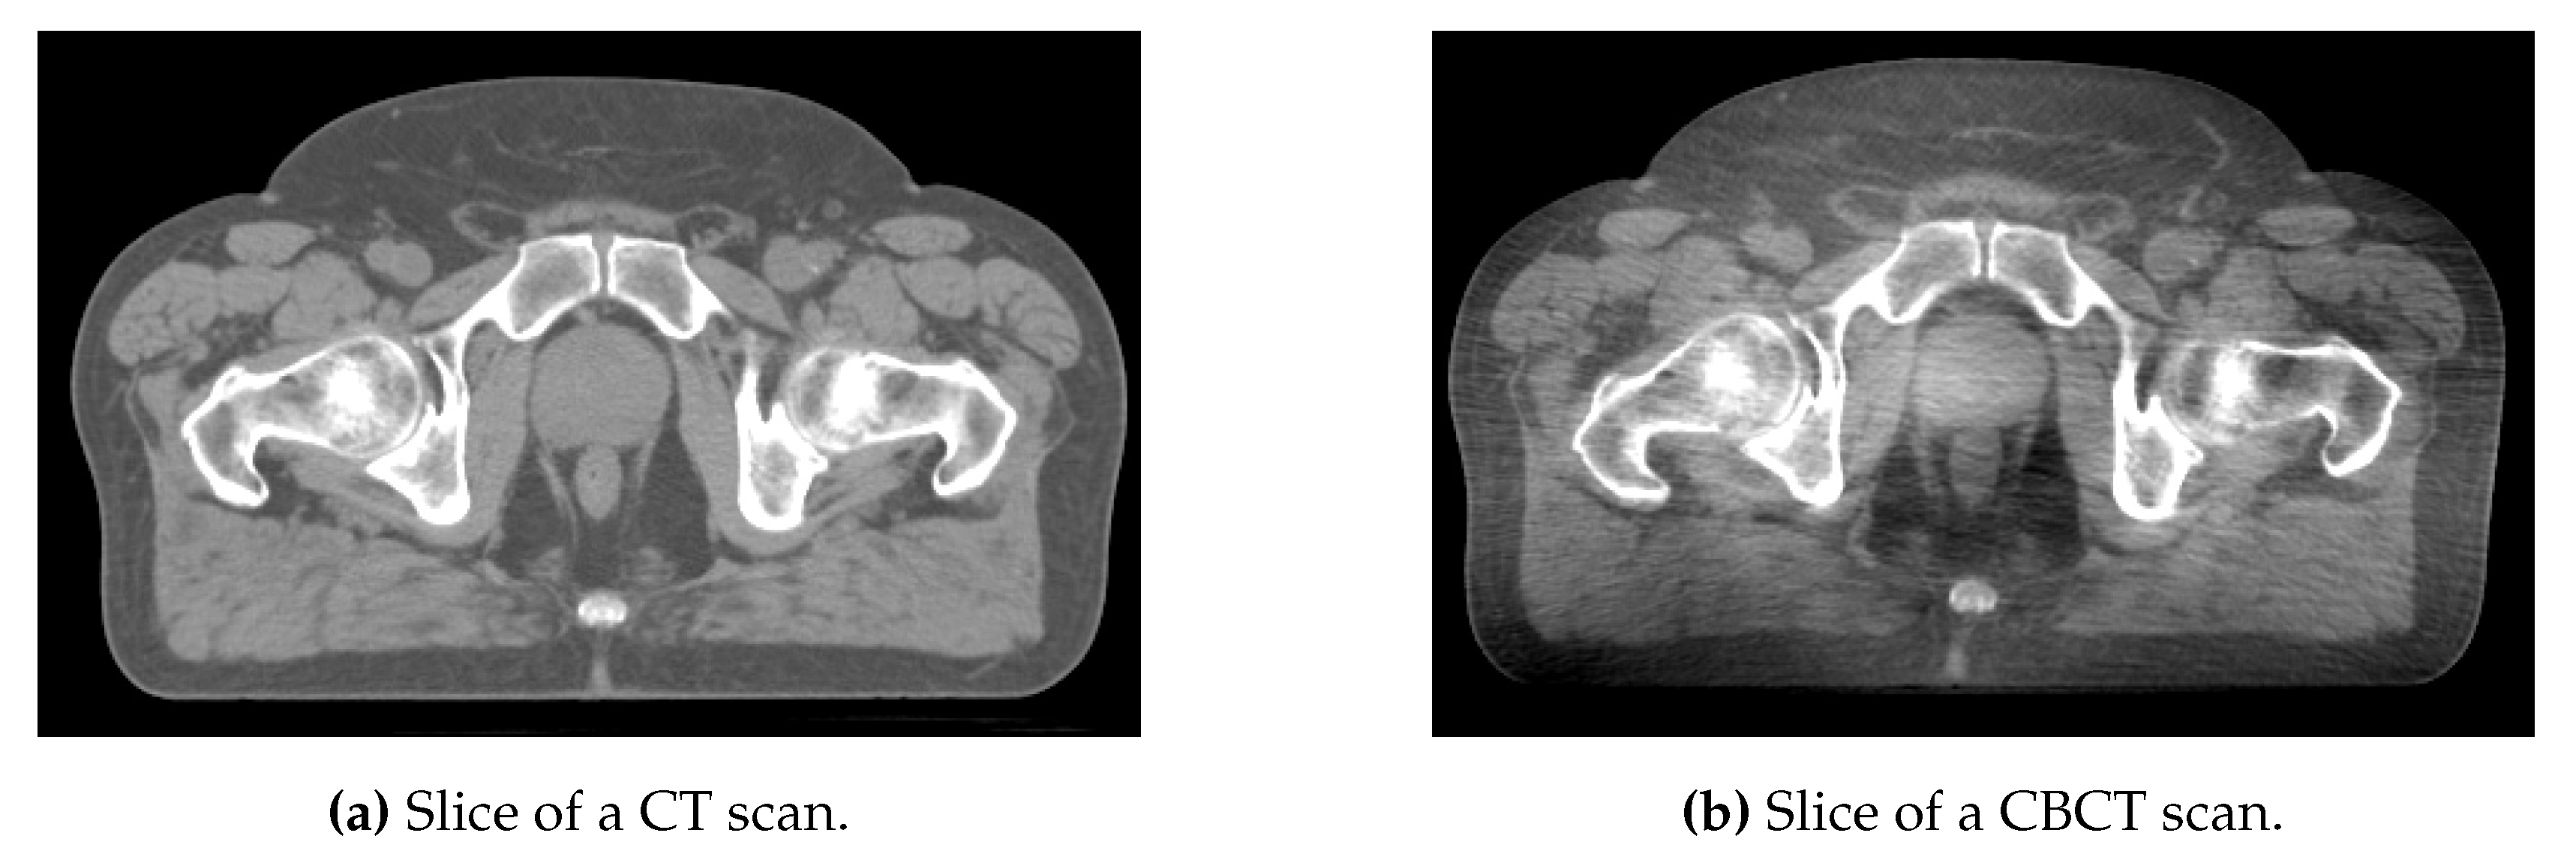

CT and CBCT are both based on X-ray propagation through the patient’s body. However, the CBCT scans are of lower quality than CT scans due to different types of artifacts, including noise, beam hardening, and scattering, as shown in Figure 1. In particular, scattering is an important limitation that could rule out the use of CBCT for radiotherapy treatment planning []. However, CBCT scans are currently used in order to detect daily variations in patient anatomy, which are particularly large in the pelvic region due to physiological function (e.g., bladder and rectal filling and voiding). Detecting such variations is important since they can impair treatment dose conformity, which means delivering too large a dose to the healthy organs (e.g., the bladder and rectum in the case of prostate cancer) and too low a dose to the clinical target volume (which simply corresponds to prostate itself for a significant proportion of patients) []. To improve treatment dose conformity in the pelvic region further, proposals have been made to change treatment plan delivery as a function of time based on observed anatomic variations [,].

Figure 1.

Comparison of CT and CBCT scans